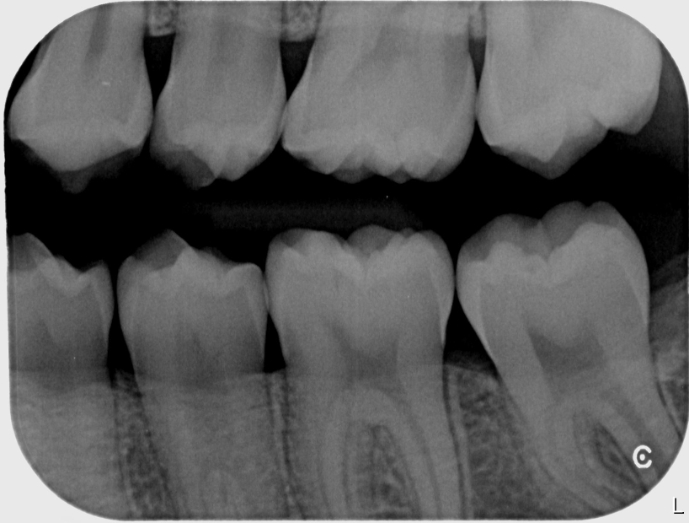

Herramienta "Gold standard" para detectar caries entre los dientes (interproximales) no visibles a simple vista y evaluar el nivel del hueso de soporte. Muestra coronas superiores e inferiores a la vez.